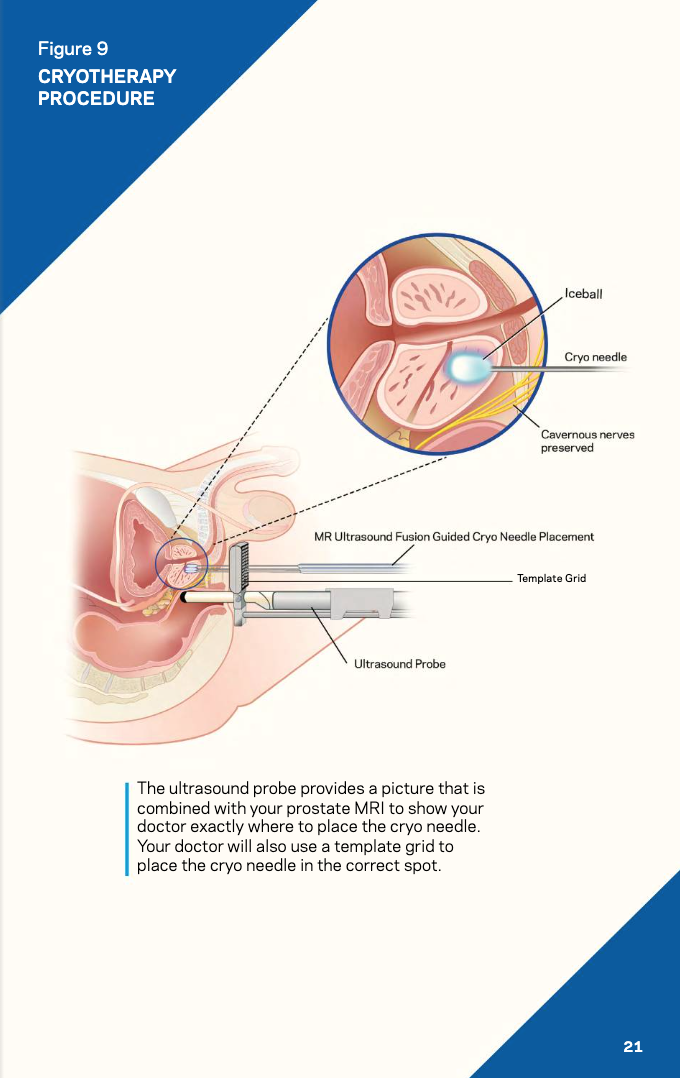

Surgical illustrations visually depict operative techniques, surgical anatomy, and complex procedures. They are created with high anatomical accuracy and serve as a visual bridge between complex surgical knowledge and learners, clinicians, or patients.

Prostate Cancer Booklet

Created clear, accurate, and visually engaging medical illustrations for a patient education booklet on prostate cancer for a hospital system. The illustrations simplified complex anatomical and clinical concepts, helping patients better understand diagnosis, treatment options, and disease progression.

Client: Northwell Hospital System

Patient Education: Prostate Cancer